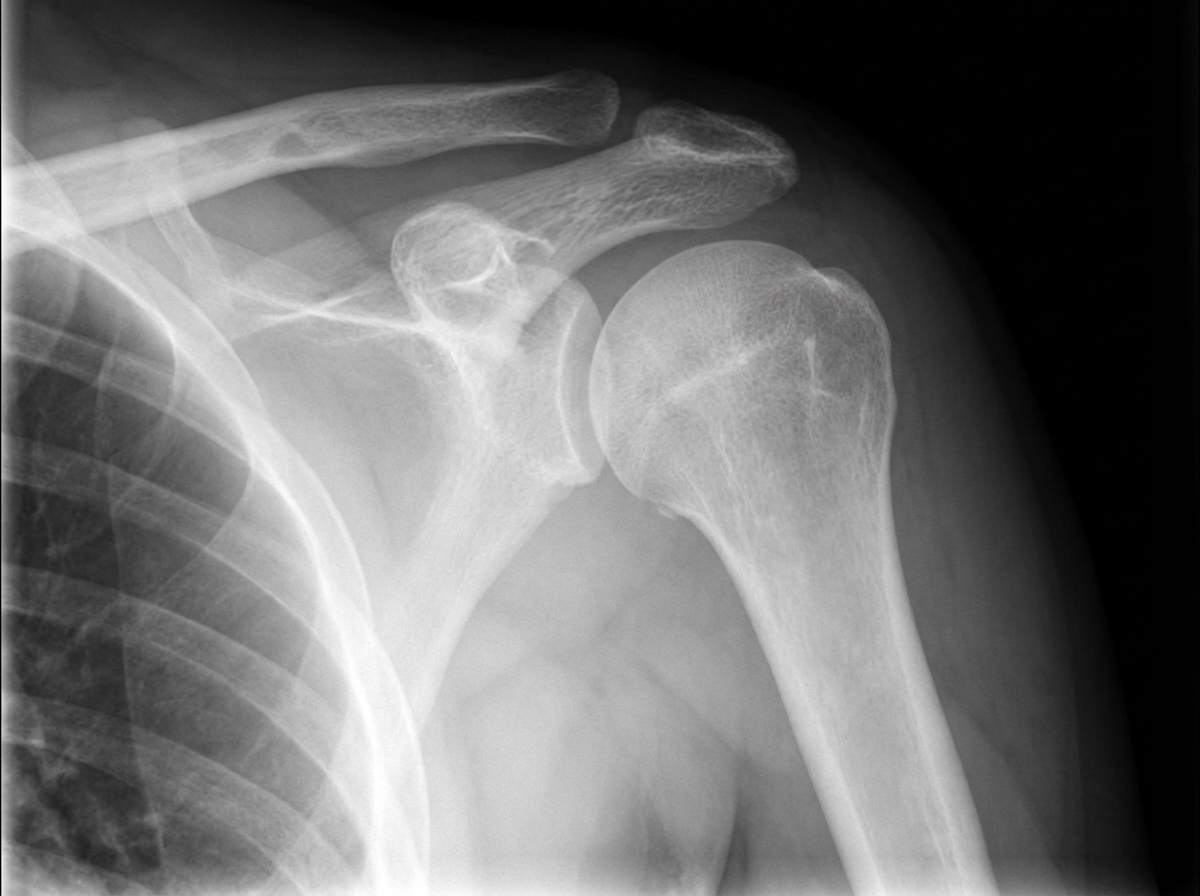

What is the abnormality shown in this shoulder radiograph?

Explanation: ***Posterior dislocation of the shoulder*** - Classic radiographic signs include the **"light bulb" sign** (fixed internal rotation of humeral head) and **trough line** (reverse Hill-Sachs lesion). - Shows **empty glenoid fossa** and **widened joint space** on AP view, distinguishing it from anterior dislocation. *Anterior dislocation of the shoulder* - Would show the humeral head positioned **inferior and medial** to the glenoid fossa on AP radiograph. - Associated with **Hill-Sachs lesion** (compression fracture of posterolateral humoral head), not the trough line seen in posterior dislocation. *Chondrosarcoma* - Appears as a **destructive bone lesion** with **chondroid matrix calcification** and soft tissue mass. - Shows **cortical destruction** and **aggressive bone changes**, not joint displacement or dislocation. *Simple bone cyst* - Presents as a **well-defined, lytic lesion** in the metaphysis with **thin cortical margins**. - Typically occurs in **proximal humerus** of children/adolescents, appearing as a fluid-filled cavity without joint involvement.